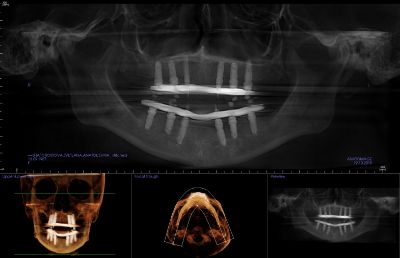

Этап 1. Подготовка

На этапе подготовки к реализации протокола  вам сделают общие анализы крови, а также конусно-лучевую томографию (КЛКТ), которая необходима для определения оптимальных мест для размещения имплантов в челюсти. На основе снимка КЛКТ в специальной программе вам составят цифровой диагностический план вашего лечения.

Этап 2. Хирургический этап

Установка имплантатов проводится при использовании специального хирургического шаблона. Этот шаблон позволит хирургу-имплантологу установить имплантаты в челюсть в заранее спланированное место, под абсолютно правильным углом и на заранее определенную глубину с точностью до долей миллиметра.